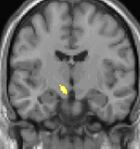

| Positron emission tomography (PET) shows brain areas being activated during pain. | ||

Positron emission tomography (PET) scans indicate the brain areas which are activated during attack only, compared to pain free periods. These pictures show brain areas that are active during pain in yellow/orange color (called "pain matrix"). The area in the center (in all three views) is activated only during cluster headaches. The bottom row voxel-based morphometry shows structural brain differences between individuals with and without CH; only a portion of the hypothalamus is different.[36]